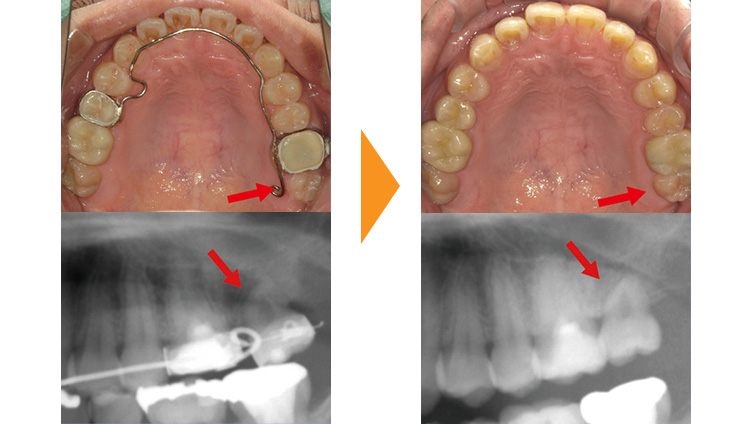

受け口タイプのかみ合わせをしているため下顎の突き上げが強く、すきっぱになってしまっている症例です。

安定性やすきまを全部埋めるためには全顎矯正が望ましい症例でしたが、患者様と相談の結果、上の真ん中の隙間を上の3番目と4番目の歯の間に集め分散させる部分矯正を行うこととしました。(すきまの位置を目立たない位置へ移動させる治療となりすきまをなくす治療ではありません)

実際に矯正器具を付け歯を動かしていくと、この症例の方も右上の犬歯がかなり「動きにくい」状態でした。

結果論としては、このような歯が動きにくい方はマウスピース矯正をしなくて正解だったなというのが正直な感想です。

元々の予定であれば上の歯の真ん中が均等に閉じるため、当初上下の正中線のずれが顕著であったため部分矯正後も正中のズレは残る予定でした。

右上犬歯が歯の移動の抵抗源となってくれたおかげで上顎の正中線が右にずれたため、図らずも矯正後は上下の正中線が一致し良い結果がたまたま起こりました。

上顎の前歯しか矯正器具をつけていないにも関わらず、下の歯との当たり方がかわったこともあり、上下のかみ合わせが浅くなってくれたことも意図せず良い結果となった点です。

今回は歯が動きにくいことにより矯正治療の予定期間が少し伸びてしまいましたが、たまたま歯並びに良い影響が出てくれました。部分矯正とは、良くも悪くも行き当たりばったりとなり、今回で言う上の前歯の隙間を閉じるという主目的以外の部分は自然に任せるという治療プランとなります。

| 初診時 | 28歳男性 |

|---|---|

| 主訴 | すきっぱが気になる |

| 期間 | 約10か月 |

| 矯正 | ワイヤー矯正 |

| 費用 | 基本検査22,000円・契約料165,000円・調整料5,500円/月(税込) |

| 治療上のリスク | 歯磨き不良の場合はむし歯になる可能性。 習癖に伴う後戻りの可能性。 |